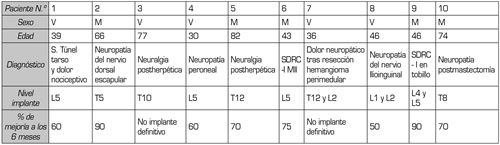

Tabla I. Características generales de los pacientes, diagnóstico, nivel del implante y porcentaje de mejoría a los 6 meses